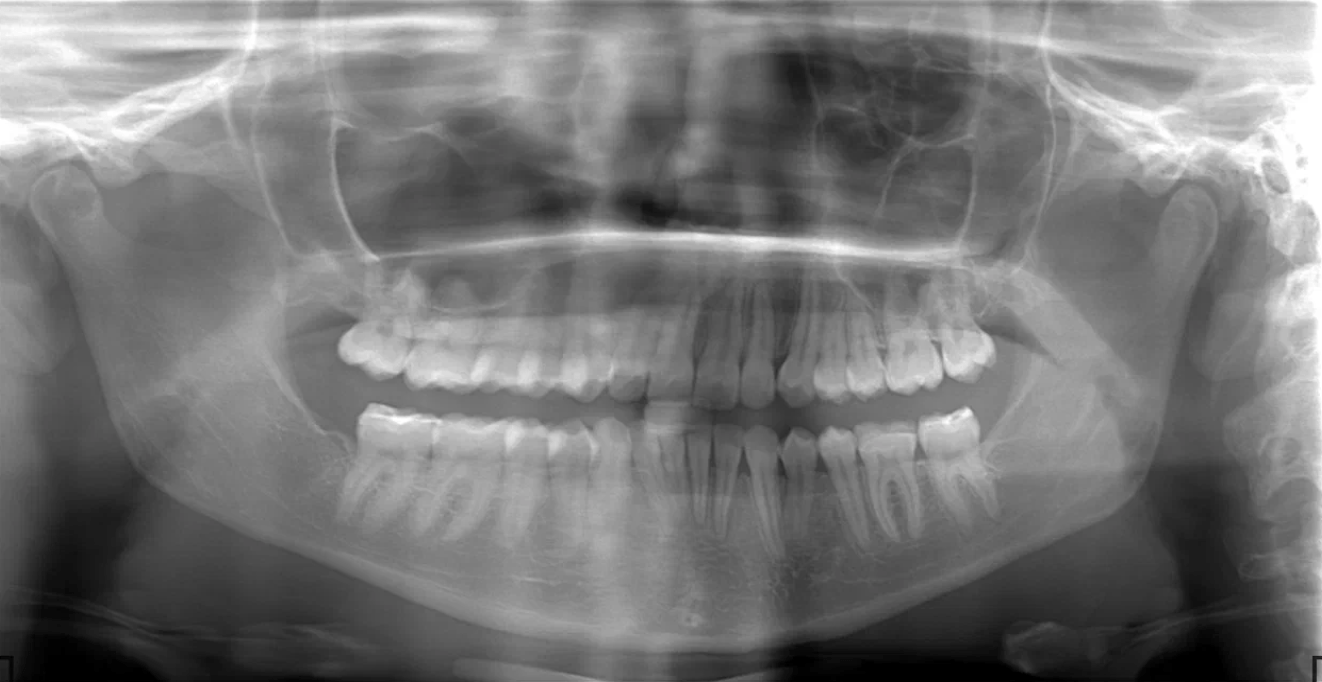

Ортопантомограмма (ОПТГ) — это обзорный рентгеновский снимок, на котором одновременно видны обе челюсти, все зубы, корни и окружающая кость. Он позволяет врачу:

Это основной метод рентгенодиагностики в стоматологии, который помогает обнаружить даже те проблемы, о которых пациент пока не догадывается.

- оценить скрытые воспаления;

- увидеть состояние зубов мудрости;

- проверить плотность и объём костной ткани;

- понять, как расположены корни и зачатки зубов.